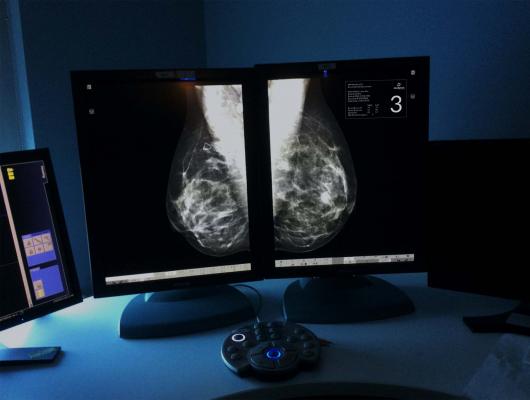

Ryan Tobin Photography for Densitas Inc.

The phase III EORTC 22922-10925 trial was conducted to evaluate what effect regional node irradiation — i.e., irradiation of the internal mammary and medial supraclavicular lymph nodes — would add to whole breast or chest wall irradiation following surgery in patients with stage I, II, and III breast cancer.

From 1996 through 2004, this randomized trial coordinated by the EORTC Radiation Oncology and Breast Cancer Groups accrued 4,004 patients with either positive axillary lymph nodes or, in the case of tumor-free lymph nodes, centrally or medially located primary tumors. The investigators concluded that regional irradiation does benefit patients with early stage breast cancer, but they also point out that these data are not applicable to patients with laterally located node-negative cancers, the largest patient subgroup in industrialized countries. They plan to continue trial monitoring for up to 20 years median follow-up.